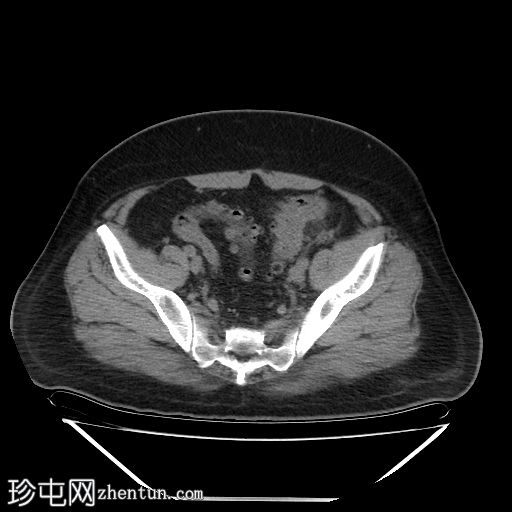

轴位

平扫

降结肠和乙状结肠可见多个小憩室,伴有少量小(亚厘米级)区域淋巴结肿大。周围脂肪和肠壁无明显增厚。

远端降结肠后壁可见一小(<15 mm)、局限性空腔,内含气泡,伴有不规则肠壁强化和轻度邻近肠系膜脂肪条索状改变。

未见脓肿、腹水、弥漫性气腹,提示IA期复杂性急性穿孔性憩室炎(局部穿孔)。